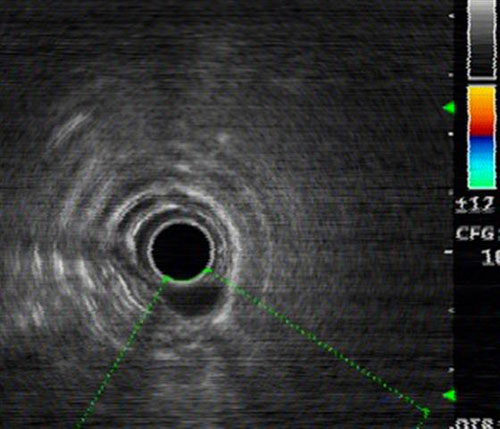

超声内镜见肿瘤起源固有肌层

患者男性,52岁,电子胃镜见食管中段一大小约1.8x1.5cm肿物,超声内镜提示起源于食管固有肌层,传统的治疗方法一般建议外科开胸手术,但其创伤大,费用高,恢复期长,也降低了患者生活质量。消化内科赵赛菊、杨力主任基于近年来科室在内镜治疗技术上的长足发展和丰富的临床经验,仔细研究了患者的病情和影像学资料,在取得患者的知情同意后,决定采用当今最新的内镜治疗技术——经内镜粘膜下隧道肿瘤切除术(STER)为患者切除肿瘤。